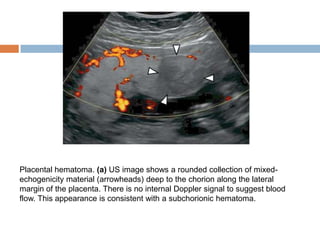

   placental hematomas appear as well-

circumscribed masses with echogenicity that

varies according to chronicity.

   They are hypoechoic or anechoic in the acute

phase, heterogeneously echogenic in the

subacute phase, and anechoic in the chronic

phase.

   Doppler interrogation should reveal absence of

internal blood flow; this finding allows

differentiation of hematomas from other placental

masses

Placental hematoma. (a) US image shows a rounded collection of mixed-

echogenicity material (arrowheads) deep to the chorion along the lateral

margin of the placenta. There is no internal Doppler signal to suggest blood

flow. This appearance is consistent with a subchorionic hematoma.

Placental Hematoma  placental hematomas appear as well- circumscribed masses with echogenicity that varies according to chronicity.  They are hypoechoic or anechoic in the acute phase, heterogeneously echogenic in the subacute phase, and anechoic in the chronic phase.  Doppler interrogation should reveal absence of internal blood flow; this finding allows differentiation of hematomas from other placental masses

Placental hematoma. (a)US image shows a rounded collection of mixed- echogenicity material (arrowheads) deep to the chorion along the lateral margin of the placenta. There is no internal Doppler signal to suggest blood flow. This appearance is consistent with a subchorionic hematoma.